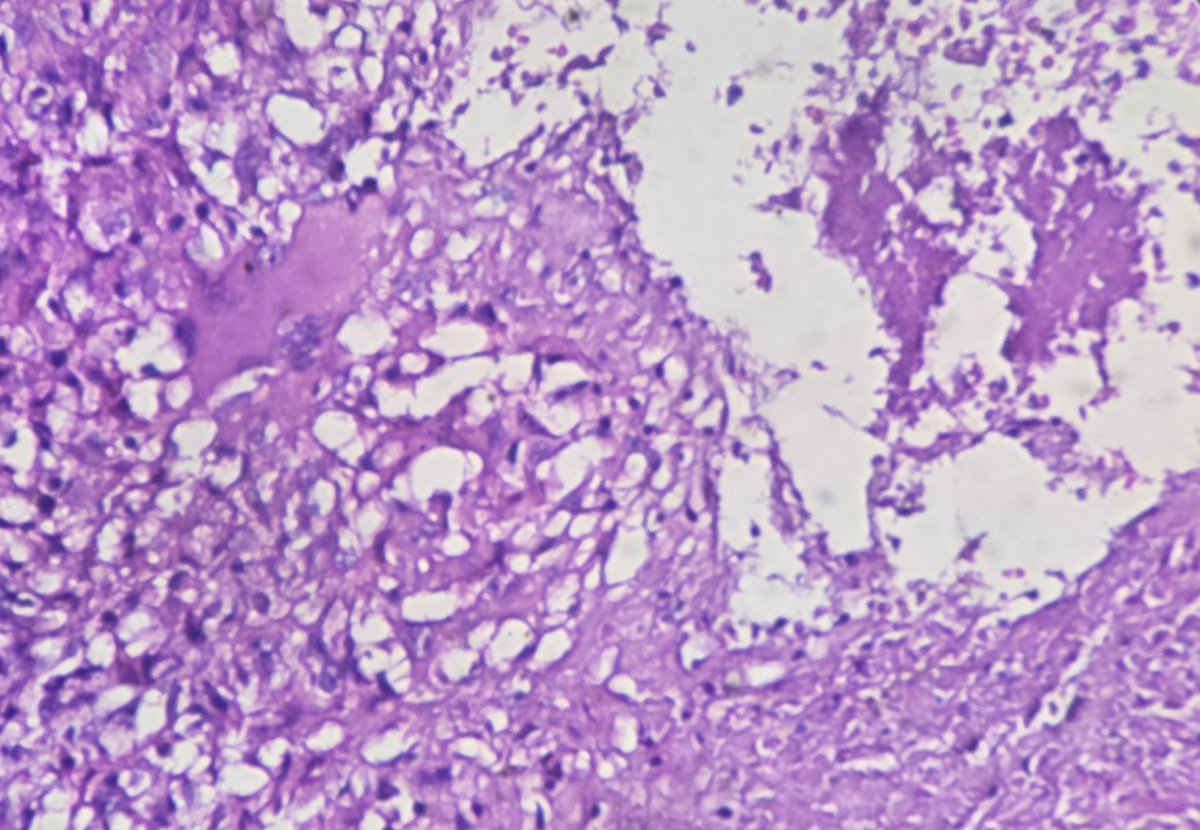

Regional lymph node metastasis of mucinous carcinoma, rectum with stage IIIC disease.

#pathology #GIPath #mucinous_carcinoma